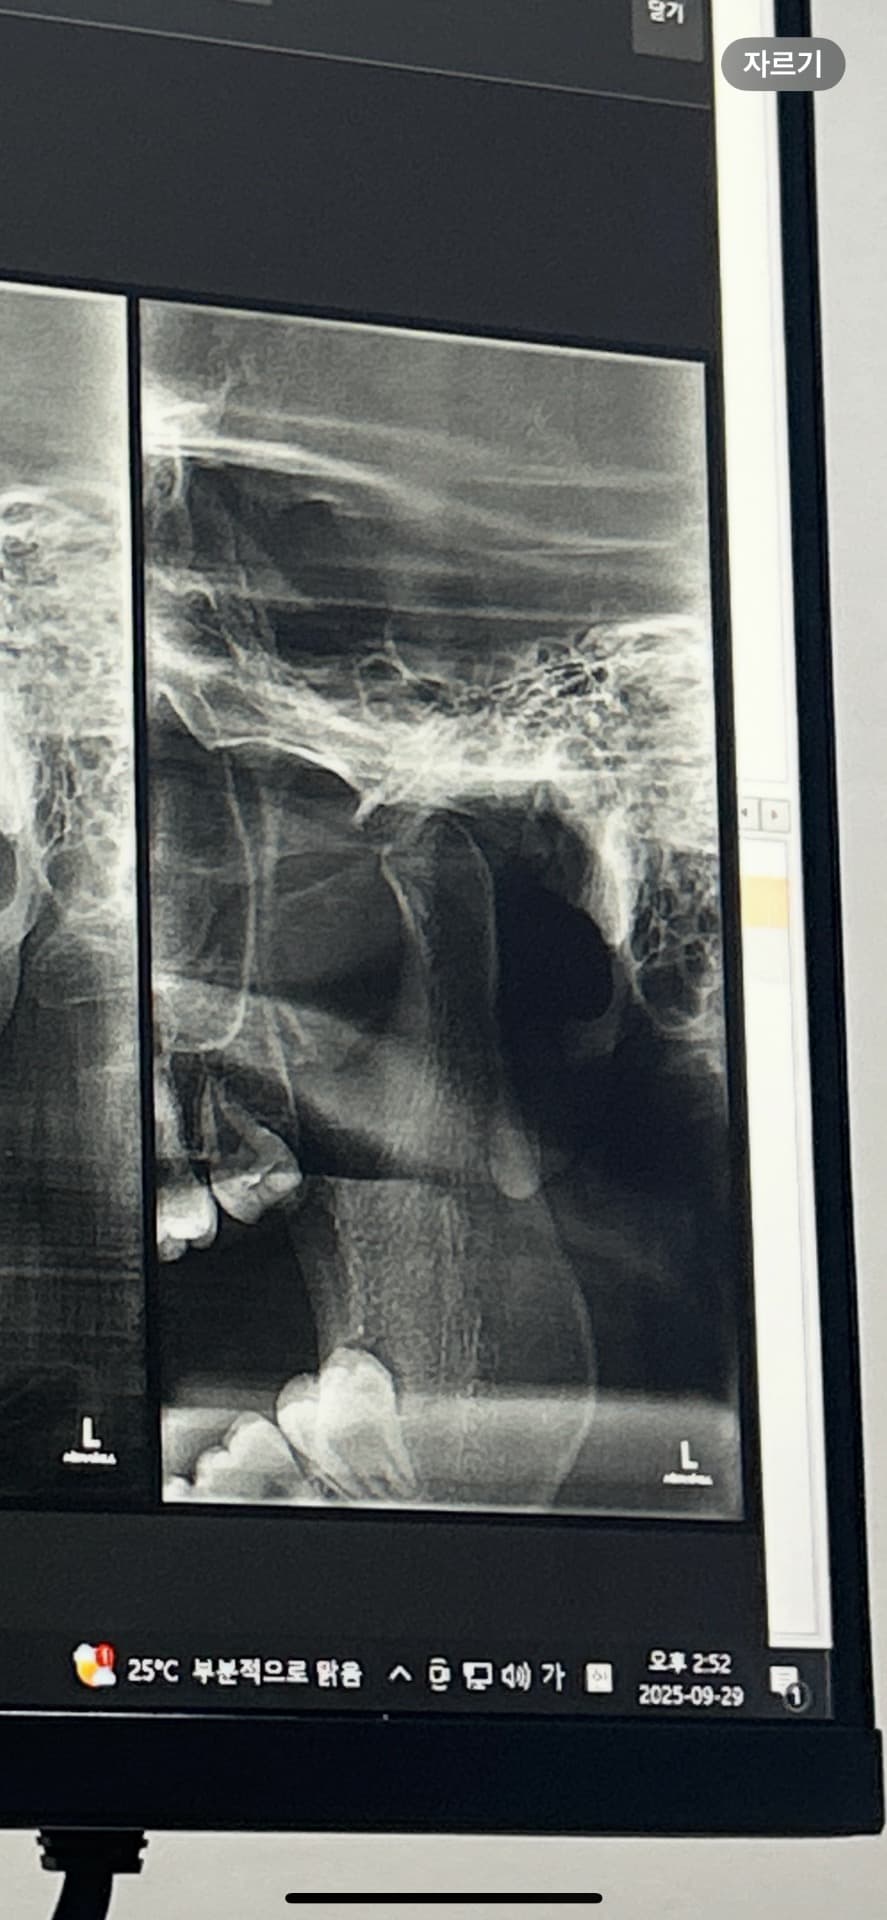

저 사진이 왼쪽 턱관절 사진인데 많이 안좋은건가요?

엑스레이상큰 문제가 있어보이진 않습니다 다만 턱관절 통증이 지속되는데 약도 별 효과가 없으면 물리치료, 장치치료, 보톡스주사, 수조작술 등이 있습니다

사진상에서는 크게 나쁜 것으로 보이지는 않습니다. 비용은 대략 100만원 정도 합니다.